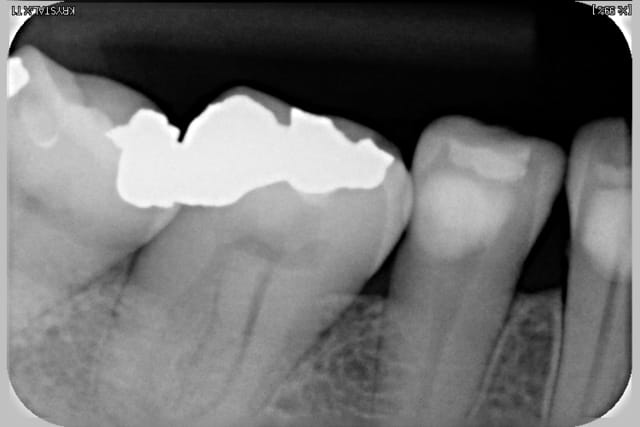

Pas de pano ? On n'a pas les même suivis , NP ( nouveau patient) = pano et radio complête.

Examen paro ? sondage et rétro ?

pour la dent 12 , il semble que ce soit lié avec la Cl-2, div-2 ( une des variante). Mais peut-être paro...on manque d'info. Pour le wax-up, c'est trop tôt.

quelques retro faites en 2009 (critiquables, je sais, ça va mieux aujourd'hui)

Voir images

On peut y voir une remodelage osseux, de tartre, l'usure de la canine